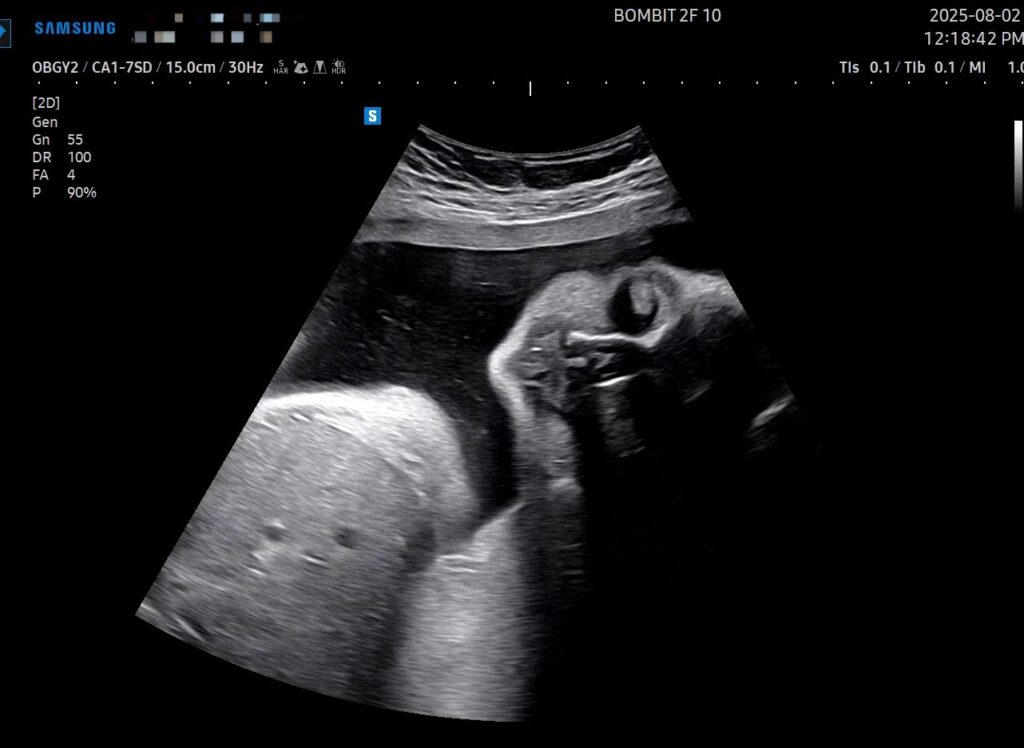

우선, 단비는 기특하게도 돌았다! 이제 더 이상 역아가 아니란다. 기특한 우리 단비!

어느덧 임신 후기에 다다르다 보니, 의사선생님도 초음파를 예전처럼 길게 봐 주시지는 않는다. 마미톡 초음파 영상 길이가 이제 1분대로 나오고, 심소도 안 들려주심.. 심장소리 못 들은게 조금 아쉬웠다 ㅜㅜ